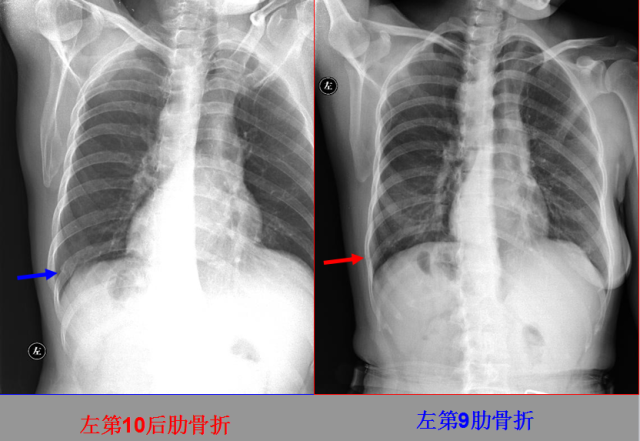

骨折篇

定义:骨折{Fracture}是指骨的完整性和连续性的折裂或粉碎。包括创伤性骨折、疲劳性骨折和病例理性骨折。 临床上以创伤性骨折*常见。